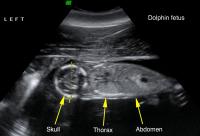

Y37 fetus ultrasound. Reproductive ultrasound image of dolphin Y37 showing an approximately 18-week gestational age fetus in a longitudinal plane, acquired in August of 2011. Dotted line shows the skull biparietal diameter, which is used to estimate gestational age and parturition date. Boat-based surveys documented that the pregnancy was successful. Dolphin Y37 was seen with a live calf in both April and August of 2012.

Dr. Cynthia Smith, National Marine Mammal Foundation